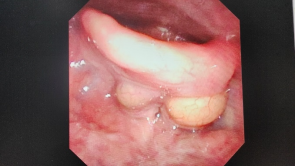

会厌囊肿

会厌囊肿是一种位于会厌部位的囊性病变。会厌是喉部的一部分,负责保护气道,防止食物和液体进入气管。会厌囊肿通常由会厌腺体的阻塞引起,导致腺体分泌物积聚,从而形成囊肿。虽然会厌囊肿一般是良性的,但它可能会引起一系列不适症状。